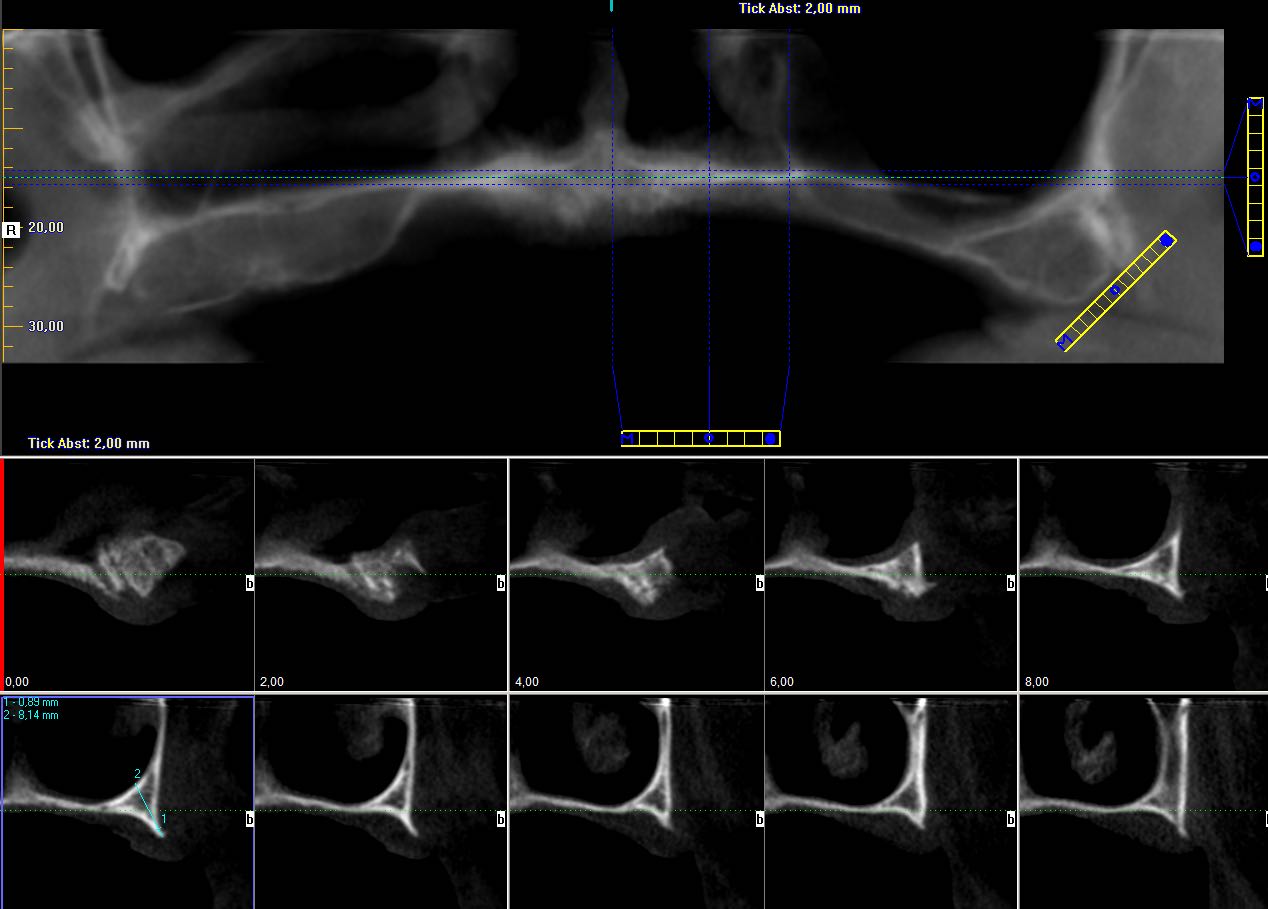

3/23 - Preoperative radiological situation – severely atrophic maxilla

Full arch reconstruction of the maxilla with maxgraft® bonebuilder - Dr. M. Erbshäuser

4/23 - Preoperative radiological situation – severely atrophic maxilla